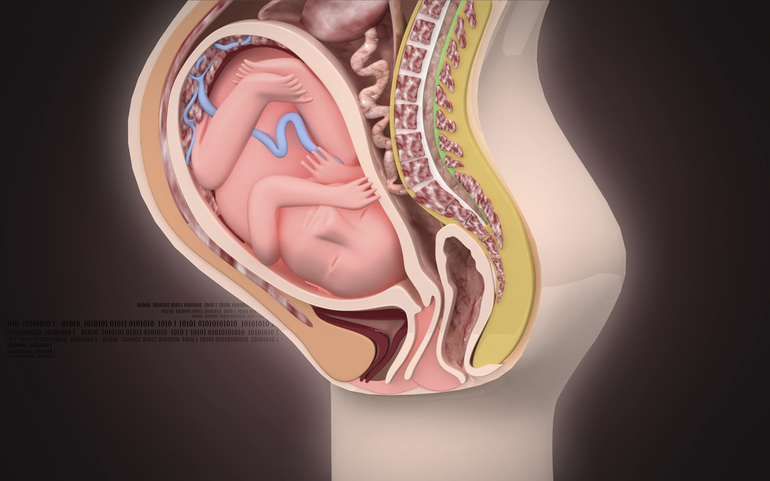

38 nedelya beremennosti 64 foto chto proishodit s malyshom i mamoj predvestniki rodov u povtornorodyashih i pervorodyashih seks i priznaki priblizhayushihsya rodov vtoraya beremennost toshnota i ponos izzhoga na 38 akusherskoj nedele (Тип файла jpg)

38 Nedelya Beremennosti 64 Foto Chto Proishodit S Malyshom I Mamoj Predvestniki Rodov U Povtornorodyashih I Pervorodyashih Seks I Priznaki Priblizhayushihsya Rodov Vtoraya Beremennost Toshnota I Ponos Izzhoga Na 38 Akusherskoj Nedele